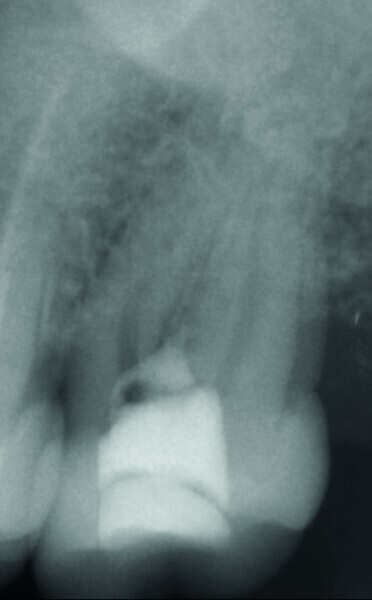

Fig. 5 : Radiographie de la fermeture de la perforation après la première visite.